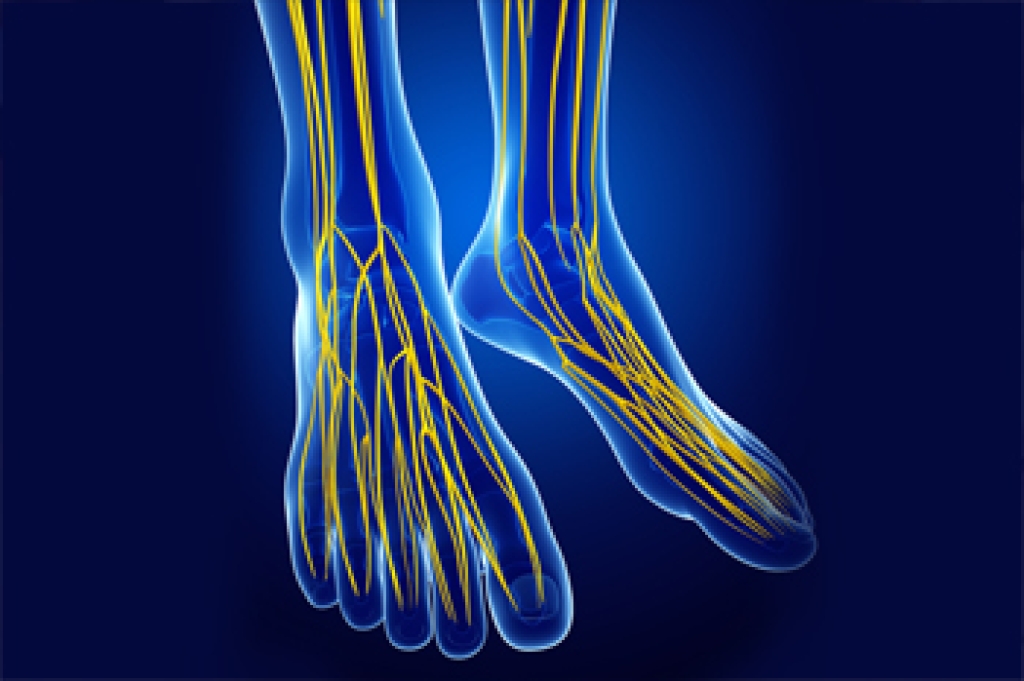

Peroneal Nerve Damage That Affects the Feet

What is termed the common peroneal nerve provides sensation to the front and sides of the leg and the top of the feet. It also controls the muscles that lift the ankle and toes upward. Symptoms felt when the peroneal nerve is injured include numbness, tingling, pain, and weakness. This damage is also responsible for a condition known as foot drop, which affects the way you walk. Damage to the peroneal nerve can be caused by something as simple as crossing the legs for too long a period, or even wearing boots that have heels that are too high. It also can be caused by a crippling genetic condition called Charcot-Marie-Booth disease or by other underlying diseases, such as diabetes. The inability to flex the foot or to take a normal footstep may indicate a peroneal nerve injury. It is not always easy to detect this type of injury, so making an appointment with a podiatrist is suggested for a thorough examination. Treatment may vary depending on the location and severity of the injury.

What Is Neuropathy?

Neuropathy is a condition that leads to damage to the nerves in the body. Peripheral neuropathy, or neuropathy that affects your peripheral nervous system, usually occurs in the feet. Neuropathy can be triggered by a number of different causes. Such causes include diabetes, infections, cancers, disorders, and toxic substances.

Symptoms of Neuropathy Include:

- Numbness

- Sensation loss

- Prickling and tingling sensations

- Throbbing, freezing, burning pains

- Muscle weakness

Those with diabetes are at serious risk due to being unable to feel an ulcer on their feet. Diabetics usually also suffer from poor blood circulation. This can lead to the wound not healing, infections occurring, and the limb may have to be amputated.

Treatment

To treat neuropathy in the foot, podiatrists will first diagnose the cause of the neuropathy. Figuring out the underlying cause of the neuropathy will allow the podiatrist to prescribe the best treatment, whether it be caused by diabetes, toxic substance exposure, infection, etc. If the nerve has not died, then it’s possible that sensation may be able to return to the foot.

Pain medication may be issued for pain. Electrical nerve stimulation can be used to stimulate nerves. If the neuropathy is caused from pressure on the nerves, then surgery may be necessary.